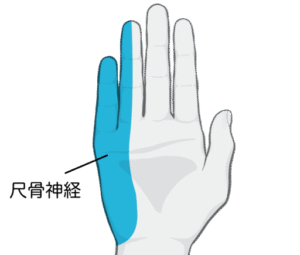

写真のように小指と薬指半分が痺れたり痛みがでます

これは尺骨神経が支配している範囲です